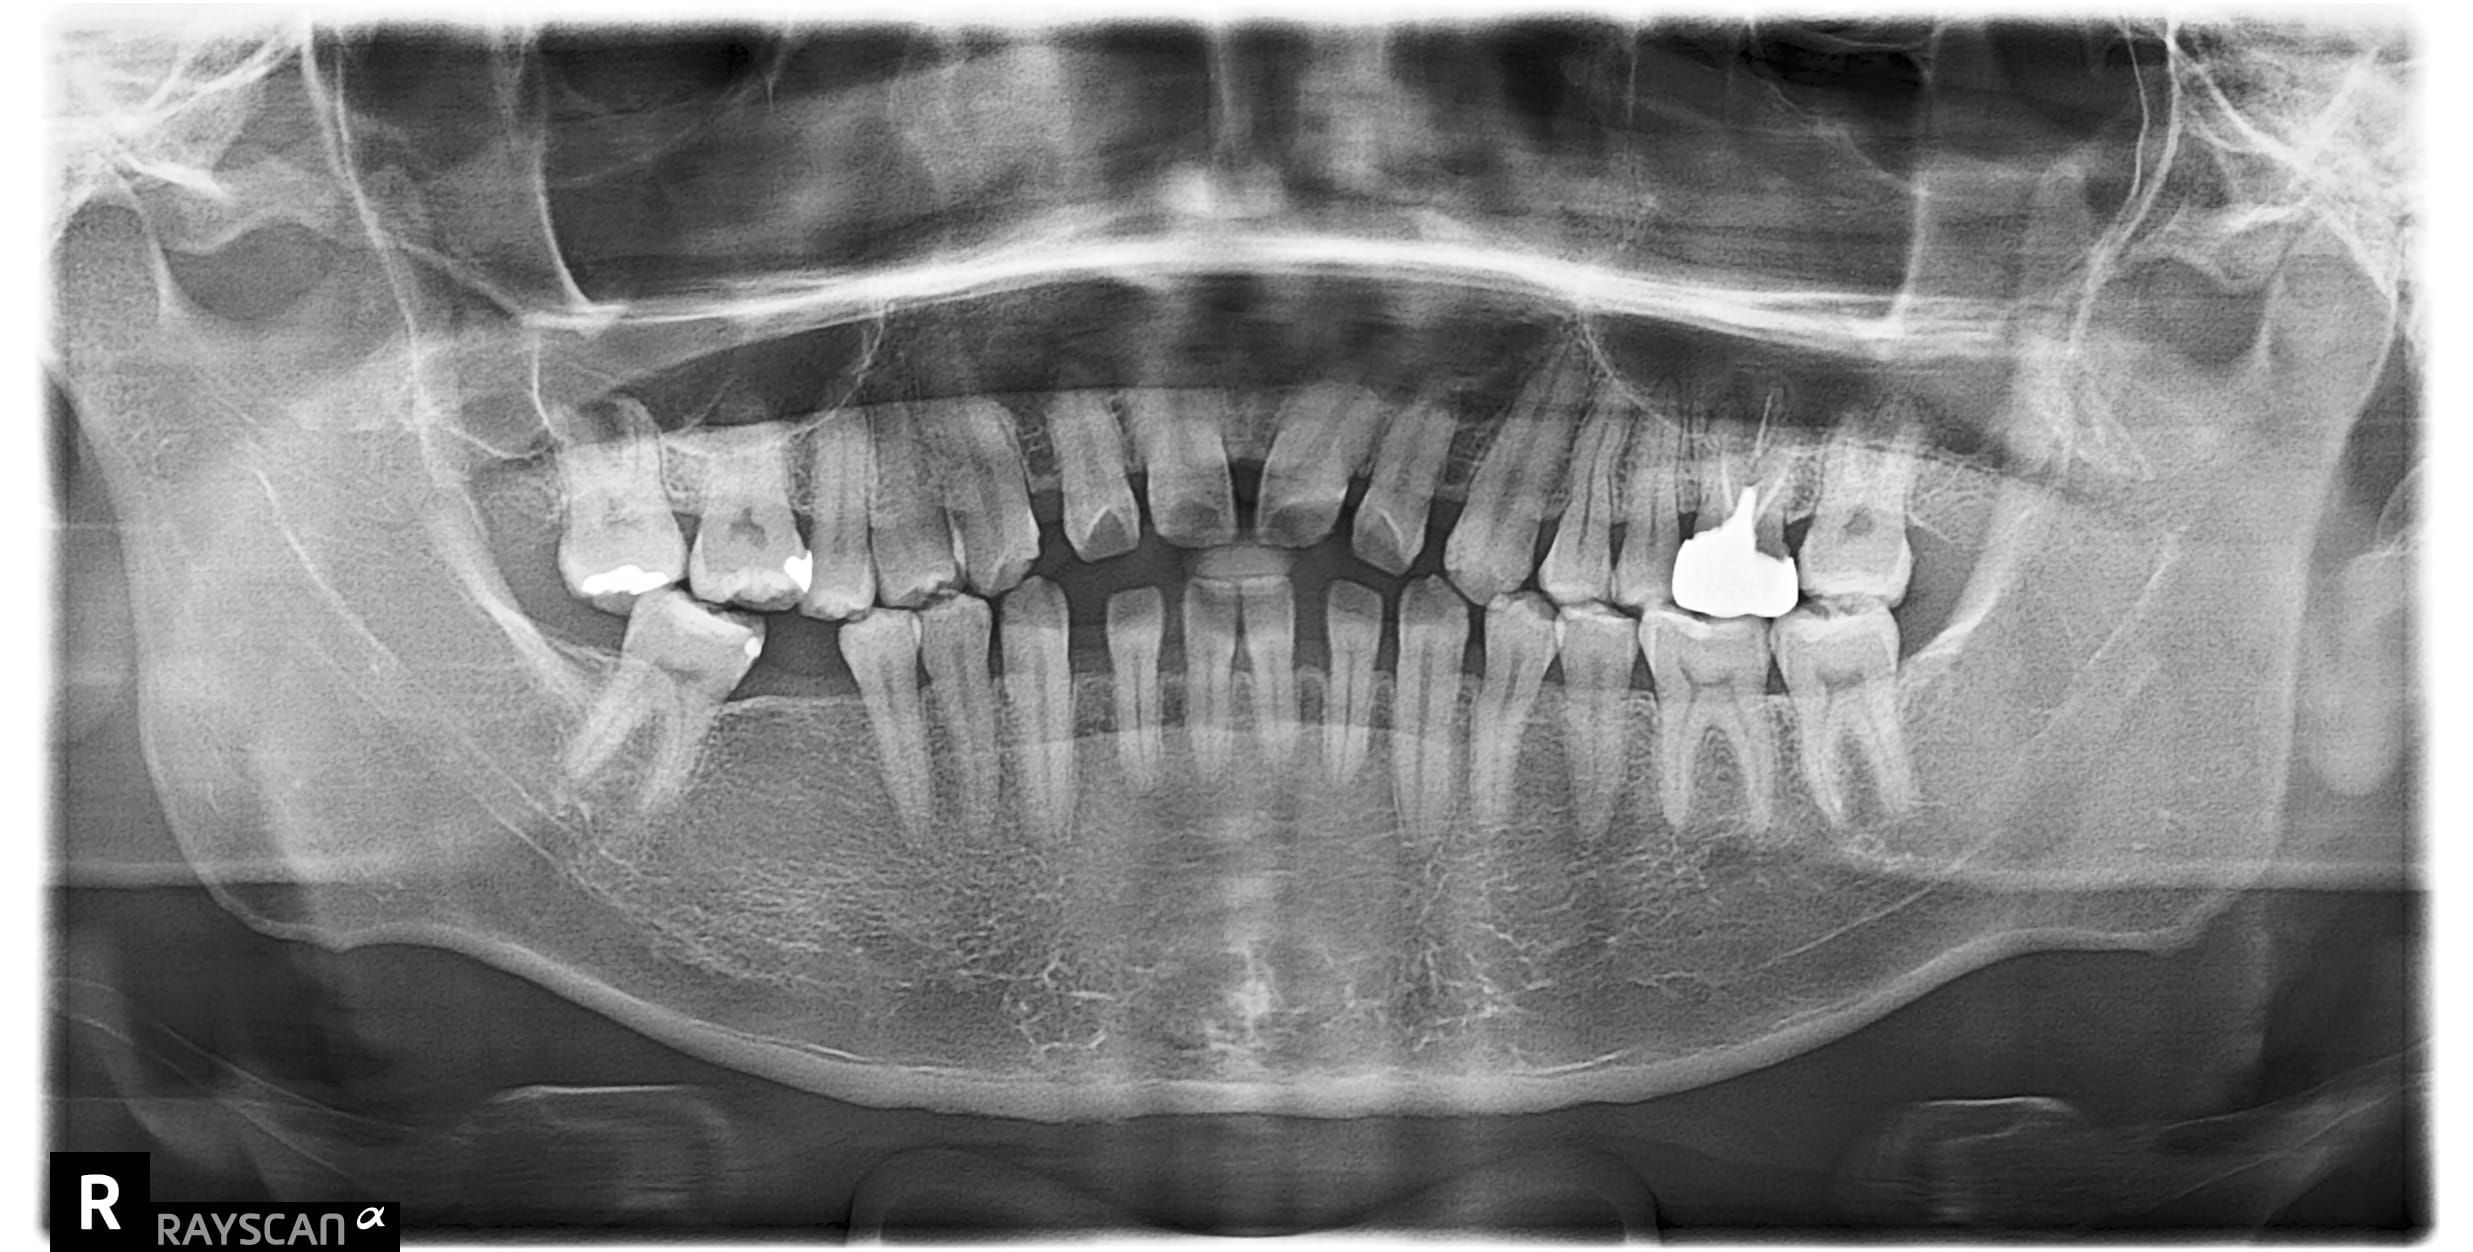

x先生左下第二小臼齒舊牙冠二次蛀牙斷掉,並影響到咬合問題 假牙不密合導致再蛀齒質脆弱咬東西斷,建議即

c先生因左上第一大臼齒根管後未裝牙套吃東西咬裂,故尋求協助治療。 牙齒裂致根部,需先拔除待傷口1-2

自述#46缺牙十年左右 想植牙改善右下第二大臼齒往前倒的狀況 骨頭狀況良好可直接植牙,等植牙接出後需

左下第一二大臼齒有膿包周囊袋過深,發現牙根斷裂 即拔即種當下清除發炎組織再補骨促進骨整合 左半邊咬合

左上第一小臼齒蛀牙缺損 齒質蛀牙嚴重導致斷裂,骨頭破壞需植入牙根時補骨促進骨整合 待3個月後骨整合完

右下第一大臼齒蛀斷 原右下第一.二大臼齒假牙相連,因右下第一大臼齒蛀牙到根部,導致兩顆假牙脫落,右下